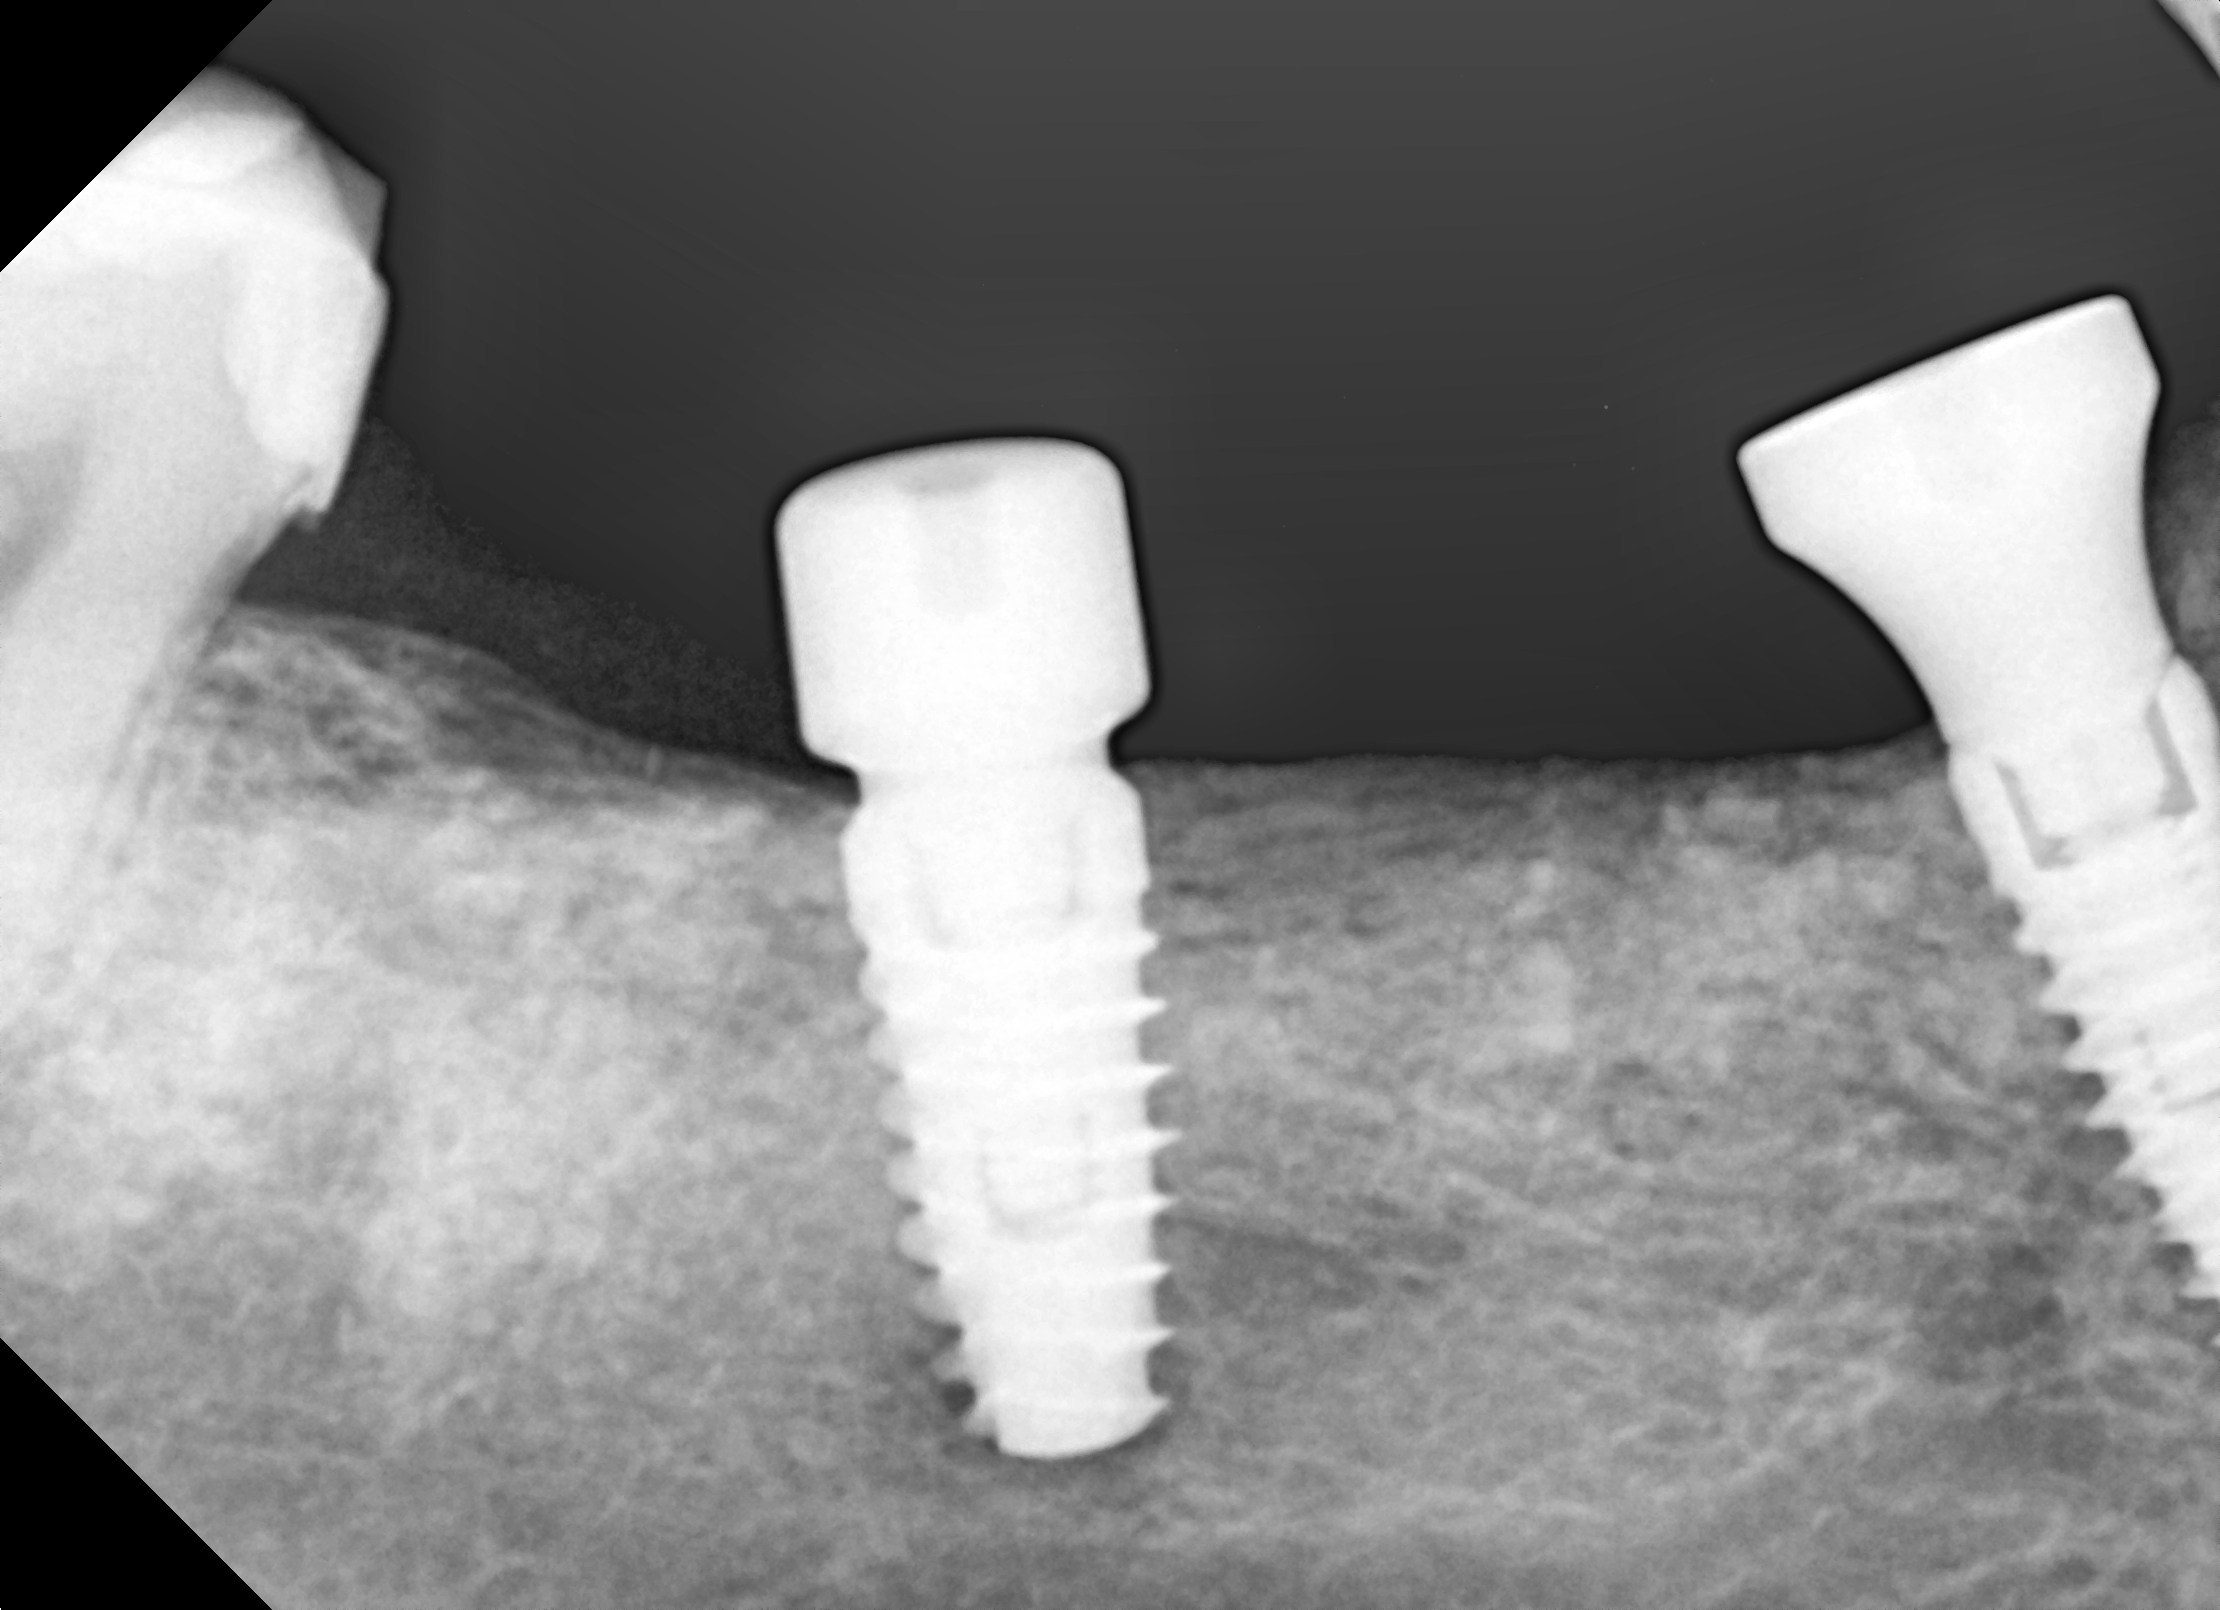

Ryc. 18. Kontrola położenia mplantu w pozycji 45.

Ryc. 19. Kontrola położenia implantu w pozycji 46-47.